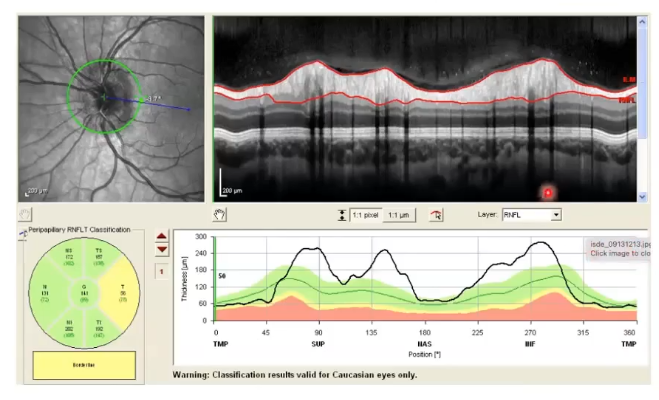

thickness comparison of cpRNFL

thickness compared to normative databse along its length and in sectors

inner limiting membrane and rnfl are the two easiest layers to segment

enables accurate measurements of thickness

right picture shows healthy eye. thicker nerve fibre layer in inferior temporal and superior temporal area

left; inferior temporal shows it is thinner as it drops off in graph.

what do the colours mean on comparisons to normative data

measurements are compared to those taken from a large number of healthy volunteers; called normative database

green= within normal limits= greater than 5th percentile of normative data

yellow= borderline, between the 1st abd 5th percentile

red= outside normal limits below 1st percentile of normative data

rnfl thickness of healthy eye

above at least 5% of healthy eyes in the database